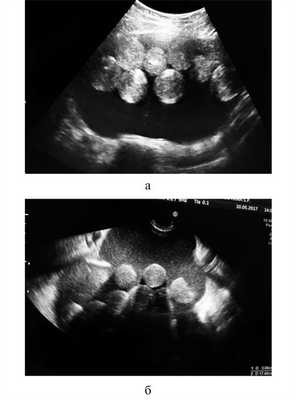

Необычными оказались результаты УЗИ органов малого таза. Матка визуализирована смещенной книзу, с четкими, ровными контурами, размером 35×31×33 мм, структура миометрия — однородная, М-эхо — 10 мм, соответствовало фазе менструального цикла (день менструального цикла на момент исследования 12-й). Шейка матки — 28×24 мм, обычного строения, канал шейки матки не расширен. Левый яичник — 41×27×31 мм, с мелкими фолликулами. В проекции правого яичника визуализировано объемное образование, выходившее из малого таза, занимавшее практически всю брюшную полость до гипогастрия. Контуры образования четкие, ровные, размер 190×100×180 мм, содержимое гетерогенное со взвесью и множественными округлыми гиперэхогенными образованиями внутри. Участков избыточной васкуляризации не выявлено. Имелось небольшое количество («следы») «свободной» жидкости в малом тазу. Заключение: объемное образование малого таза и гипогастрия, вероятнее всего, исходящее из правого яичника (Тератома? Паразитарная киста?) (рис. 1). Рис. 1. Эхографическая картина новообразования (а, б — различные сечения). Видны свободно плавающие в кистозной полости гиперэхогенные «шары» примерно одинакового строения и диаметра, на основании чего заподозрено наличие паразитарной инвазии.

Данный случай примечателен не столько своими клиническими особенностями (хотя для доброкачественного дермоида нехарактерны такой быстрый рост, анемия, асцит, увеличение концентрации онкомаркеров и нарушения уродинамики), сколько эхографической картиной. Наличие свободно плавающих в полости кисты округлых образований примерно одинакового размера (рис. 3), Рис. 3. Новообразование вскрыто. Видно жидкое содержимое, в котором свободно плавают шаровидные структуры. несмотря на отрицательные результаты исследований, проведенных паразитологом, и отсутствие эозинофилии, не позволяло исключить паразитарную кисту вплоть до момента операции. Применение помимо УЗИ также КТ и МРТ с усилением не способствовало уточнению диагноза.